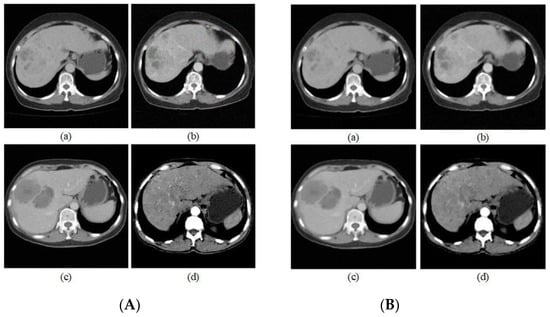

| a | b | c | d | |

|---|---|---|---|---|

| PSNR | 27.39 | 29.86 | 27.46 | 27.19 |

| SSIM | 93.70% | 89.51% | 94.46% | 94.96% |